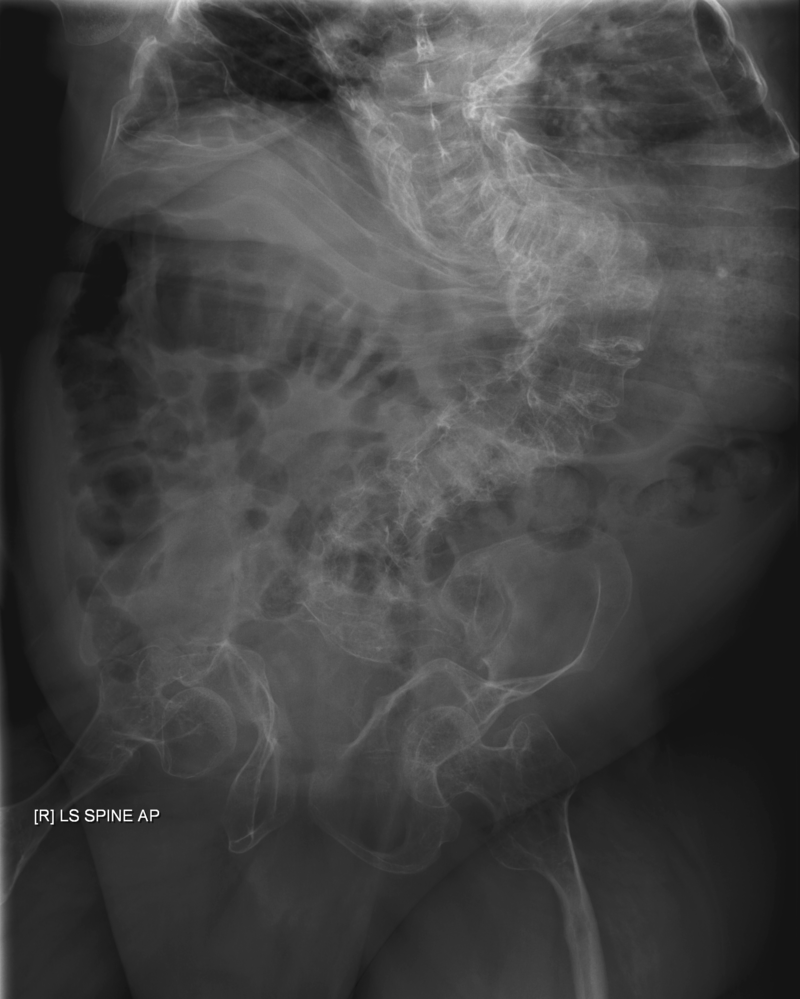

Rickets

Rickets is defective mineralization of osteoid that effects children.

Osteomalacia is defective mineralization of osteoid that effects adults.

Both rickets and osteomalacia are related to vitamin D deficiency.

Low vitamin D levels in children cause improper bone mineralization, which causes rickets.

Common features of rickets include:

- Pigeon breast deformity

- Rachitic rosary chest

- Frontal bossing

- Large forehead

Rickets is pathognomonic associated with “pigeon-breast deformity” on chest X-ray

The pigeon chest deformity is the inward bending of the ribs with anterior protrusion of the sternum.

Rachitic rosary in children is caused by osteoid deposition at the costochondral junction.

Frontal bossing or having a larger forehead due to osteoid deposition on the skull is another common symptom of rickets in children.